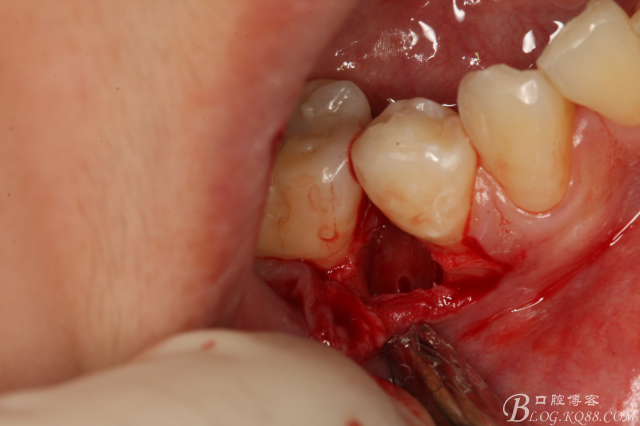

圖10.高速裂鉆垂直分根

圖11.形成牙根中央一個約5mm長、2mm寬溝槽。

圖12.微創(chuàng)牙挺放入制備好的溝槽內(nèi)。

圖13.取出一塊牙根。給余留 牙根騰出脫位空間